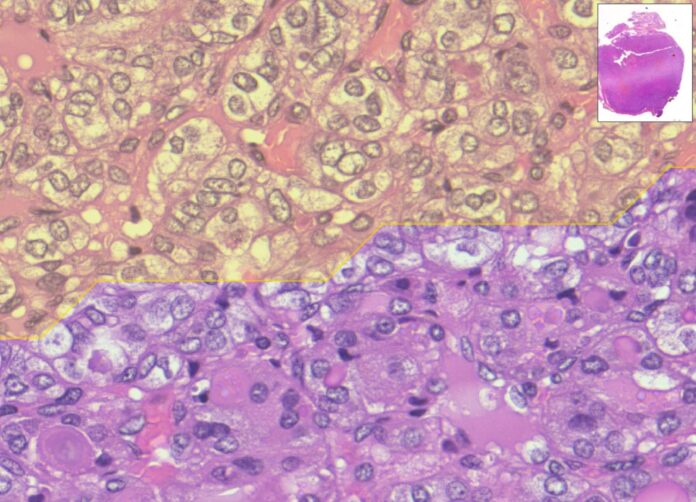

Si tratta di un algoritmo di digital pathology in grado di analizzare immagini istologiche ad altissima risoluzione in grado di fornire un aiuto significativo ai medici nella diagnosi di tumori.

Il sistema utilizza reti neurali profonde (strumenti di deep learning, dunque basate sull’Intelligenza Artificiale) addestrate su migliaia di campioni digitalizzati con scanner molto potenti (l’immagine ricavata dai vetrini istologici su cui si trovano le cellule da analizzare) per identificare automaticamente aree, cellule, marcatori sospetti, spesso difficili da rilevare da parte dell’occhio umano.

L’Intelligenza Artificiale analizza l’immagine del campione e si concentra in modo rapido sulle aree che meritano l’attenzione dei medici, velocizzando in tal modo la diagnosi e rendendola più efficace. Più nello specifico, il sistema sviluppato nella ricerca mette in campo un “doppio occhio”, due reti neurali che lavorano in sequenza: un primo “occhio digitale” coglie i dettagli delle cellule, un secondo “occhio” considera la visione d’insieme dell’immagine. Integrando le due letture, MiThyCA indica le aree che è opportuno analizzare per prime.

Negli studi condotti su casi di carcinoma tiroideo, l’algoritmo ha raggiunto un’accuratezza diagnostica paragonabile a quella di un team esperto, fornendo un secondo parere, accanto a quello umano oggettivo e riproducibile.